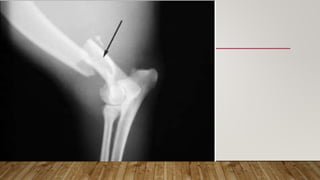

This document discusses radiology and the use of x-rays. It begins with an introduction to radiology and x-rays, noting their importance as the "father of medical investigations." It then discusses anatomy as seen on radiographs and whether x-rays are enough. The document goes on to compare gross views to radiological views, noting what each can and cannot show. It highlights important figures in the development of radiology, from x-rays to CT, MRI, and ultrasound. Specific anatomical structures visible on upper and lower limb x-rays are listed. The document concludes by discussing how pathologies appear on x-rays and the importance of clinical history and knowledge when interpreting radiological images.